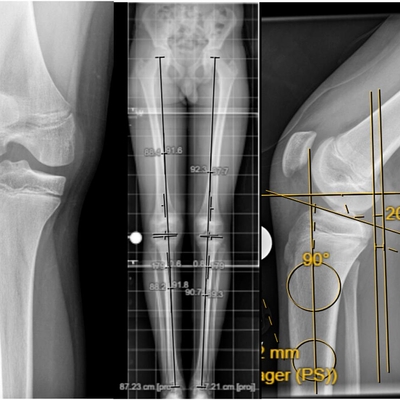

Click on an image below to view more info.